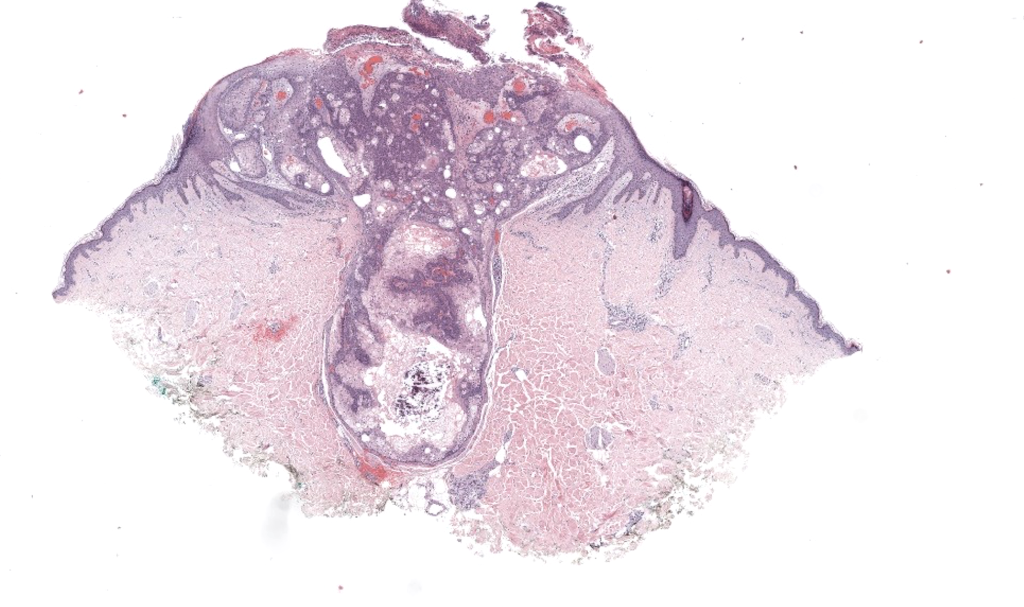

Histología: lóbulos con periferia basaloide y centro de sebocitos maduros; >50% sebocitos. Shalin 2010.